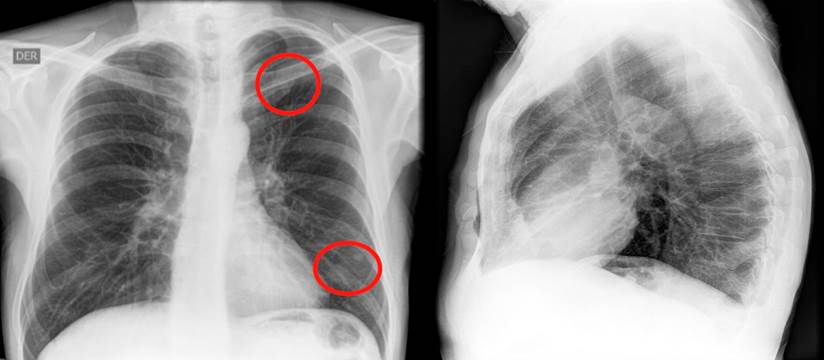

En un nuevo control endoscópico, se encontró pancolitis ulcerativa y pseudopólipos, que en comparación con la colonoscopia previa, evidenció una progresión de la enfermedad, por lo que se contempló el inicio de una terapia biológica. Se solicitaron pruebas de tuberculina (Purified protein derivative, PPD), serología para hepatitis A, B, C y una prueba de VIH. Se realizó además una radiografía de tórax, en la que se observó la presencia de un nódulo en el lóbulo superior izquierdo y otro en el lóbulo inferior, de 6 mm cada uno (Figura 1). La tomografía computadorizada de tórax confirmó dichos hallazgos (Figura 2).